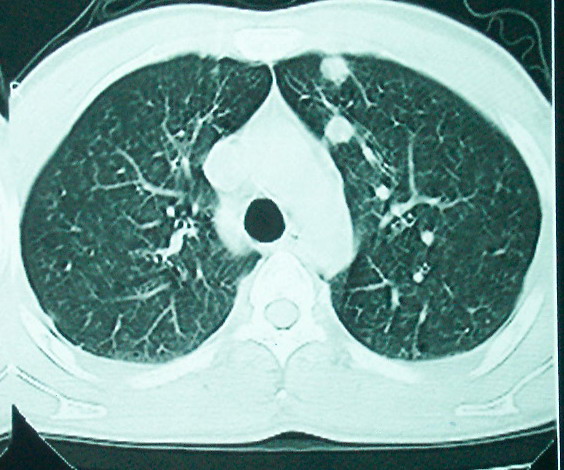

m      37y      发热   咳脓痰月余      ct肺脓肿但住院抗炎治疗后双肺内结节不知该如何解释

治疗后见左肺下野病灶较前缩小但双肺内结节影似无变化请较各位老师该如何下结论    治疗前wbc14.5 治疗后wbc 11.0

血源性肺脓肿,一般由原发感染灶引起脓毒败血症,在肺部形成小脓肿,病变变化快,容易形成肺气囊,脓气胸,主要与转移瘤鉴别,通过临床病史可分

结合临床发热,咳痰考虑为血源性肺脓肿,不过双肺结节又在肺的边缘,还是小心一点,抗炎后复查吧

除了肺内多发结节和左肺下叶的浓疡病灶,还应注意满肺散在的小结节影,还有右上肺前段支气管内膜不光整这些细节,结合病史,肺内多发结节应考虑结核性肉芽!